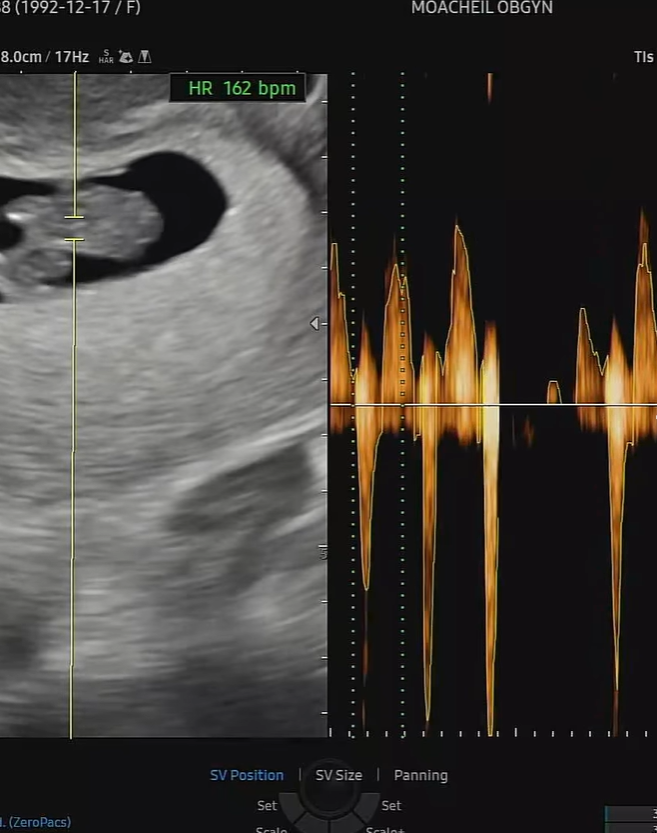

La cantante Keumjo anunció que está embarazada de su primer hijo. La artista compartió la noticia el 14 de febrero mediante sus redes sociales oficiales. Publicó fotos junto a su esposo Baek Kibum sosteniendo una prueba de embarazo. También mostró ecografías que confirmaron el avance de su gestación.

Keumjo reveló que cursa actualmente 12 semanas y un día de embarazo. La artista escribió el mensaje: “Embarazo a punto de revelarse”. La publicación incluyó imágenes íntimas que reflejaron la emoción de la pareja. El anuncio confirmó que el nacimiento está previsto para agosto.

La intérprete contó que recibió la noticia el 17 de diciembre, el día de su cumpleaños. Keumjo afirmó: “Ese día vi las dos líneas como si fuera un regalo”. La artista explicó que ese momento marcó profundamente su vida personal. Desde entonces, la pareja comenzó a preparase para la llegada del bebé.